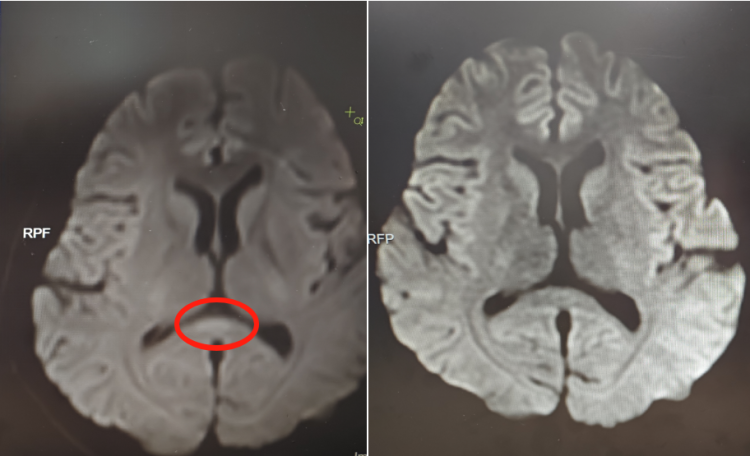

▲治疗前(左)核磁共振提示胼胝体压部病变

该院神经内六科医生接诊后,初步判断为脑炎。完善血清、脑脊液检测等,结果不支持颅内感染及自身免疫性脑炎,进一步完善细胞因子等炎症指标,结合核磁共振等,最终诊断阿婷为副感染性脑病。